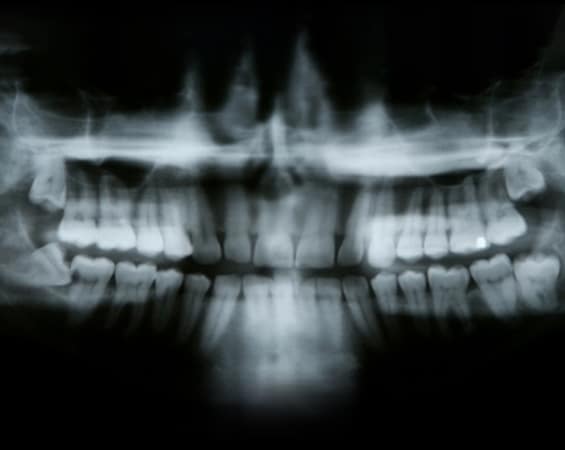

A tooth becomes impacted when there is not enough room to accommodate the space in the dental arch and growth becomes impossible. After surgery to remove an impacted tooth, mild discomfort and some swelling is expected. This is part of the process and should not alarm you. You may use cold compresses to alleviate the swelling. In addition, your doctor will prescribe pain medication, which should be taken as directed. Patients are also advised to favor the extraction area and modify their diet for a few days to allow for healing.